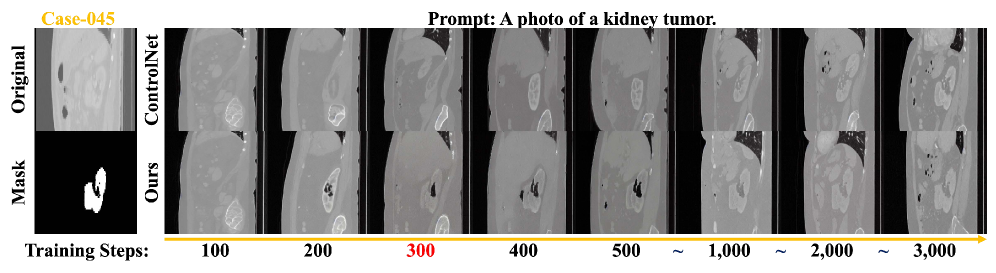

Refer to caption

Figure 2: Visualizing the difference between ControlNet and our method in training convergence and data fitting.

Fig. 2 demonstrates that the teacher model’s adaptive regularization accelerates the student model’s data fitting within approximately 300 steps, mitigating the sudden convergence phenomenon in ControlNet [36].